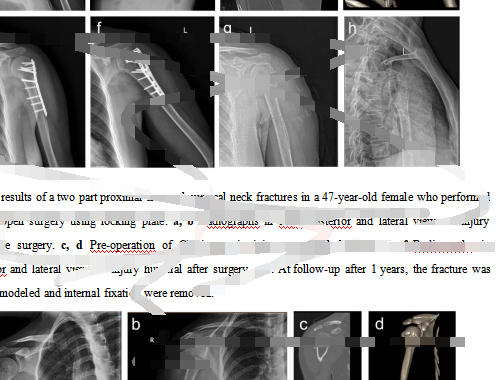

在另一家“论文工厂”,当记者表示着急想发医学方面顶级期刊,对方推荐给记者一篇已基本写好的颈部骨科研究英文论文,并发来部分内容供记者审核评阅,总“标价”3.75万元。

“论文工厂”发给记者的一篇已基本写好的颈部骨科研究英文论文的部分内容